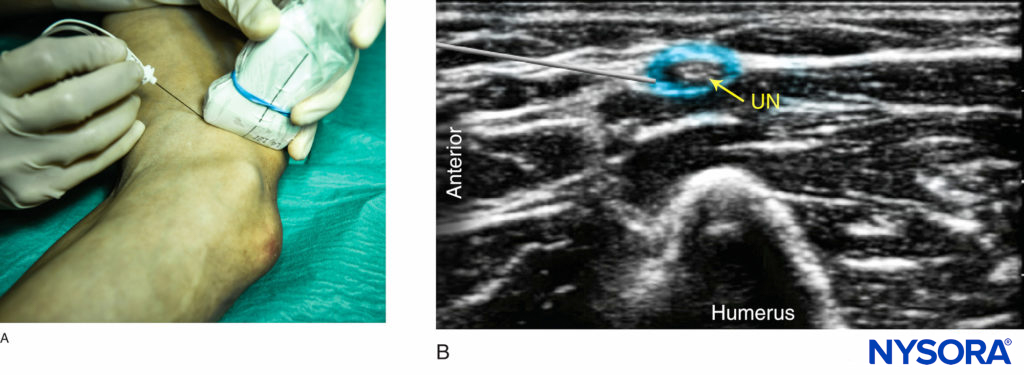

The ulnar nerve is identified at the posteromedial aspect of the elbow, few centimeters proximally to the crease, as a hyperechoic oval “honeycomb” structure immediately underneath the brachial fascia and superficial to the triceps muscle (Figure 5). The ulnar nerve can be traced distally toward the ulnar notch, where it appears as a round hypoechoic structure diving into the bony ulnar sulcus before entering the forearm underneath the flexor carpi ulnaris muscle. Sliding the transducer proximally, the nerve can be easily traced back to the axilla along the medial aspect of the arm.

FIGURE 5 (A) Anatomy section of the distal arm at the level of the elbow. (B) Sonoanatomy of the ulnar nerve proximally to the elbow crease.

The Ulnar Nerve

The transducer is then positioned more medially until the ulnar nerve is identified. The needle is inserted in-plane from either side of the transducer (the anterior to posterior side is often more ergonomic) (Figure 8a). After negative aspiration, 4–5 mL of local anesthetic is injected (Figure 8b). If the spread of local anesthetic is inadequate, slight adjustments can be made and a further 2–3 mL administered.